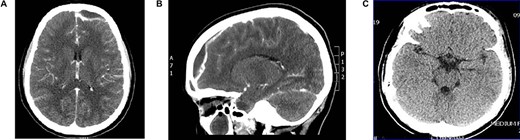

Young girl presented with unresolving sinusitis associated with fever, headache, vomiting and drowsiness. Diagnosed on CT brain as a case of SDE (Fig. 3A and B) as a complication of frontal sinusitis. The patient was managed by systemic intravenous antibiotic. Endoscopic frontal sinusotomy and frontal mini craniotomy to drain the empyema by the neurosurgery team. The patient recovered well with no complications as shown in follow-up CT scan (Figure 3C).

(A) axial CT brain with subdural empyema, (B) sagittal CT scan with subdural empyema and (C) post drainage CT brain with complete resolution of subdural empyema.